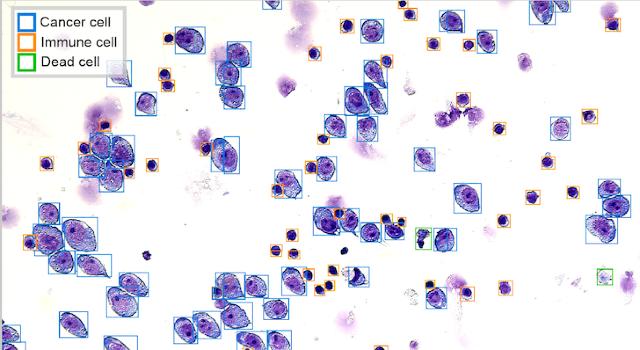

More than 50% of patients with cancer do not respond to the drug given to them. We developed a personalized, ex-vivo, single-cell method that can test 120+ drugs in parallel on a patient's live cancer and healthy cells. The test can identify which drugs and combinations are most effective for this patient, helping oncologists make better treatment decisions. Clinical trials consistently demonstrate that patients whose treatment was guided by our platform achieve significantly longer overall survival compared to those receiving the standard of care.

PrevisionOne test